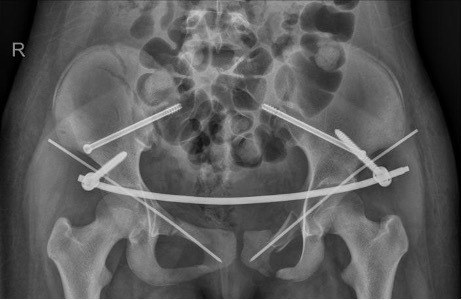

手术过程中,创伤骨科主任樊仕才带领团队充分利用机器人辅助系统的精准定位能力,通过牵引架复位骨盆,恢复骨盆形状,完成骨盆成形。随后,在C型臂透视引导下,利用机器人精确设计并打入多枚螺钉,这些螺钉不仅位置精确,而且长度适中,确保了骨折部位的稳定固定。

在处理骨盆后环骨折时,医生通过机器人系统设计了多个螺钉通道,并成功打入了多枚适宜长度的螺钉,使骨盆后环得以完美成形。这一步骤不仅要求极高的技术精度,还需要对骨盆结构有深入的了解和把握。

此外,手术团队还利用了机器人辅助系统对髋臼骨折进行闭合复位,微创固定。在机器人的精确引导下,手术团队成功地将骨折部位复位并固定,为患者的康复奠定了坚实的基础。

术后影像